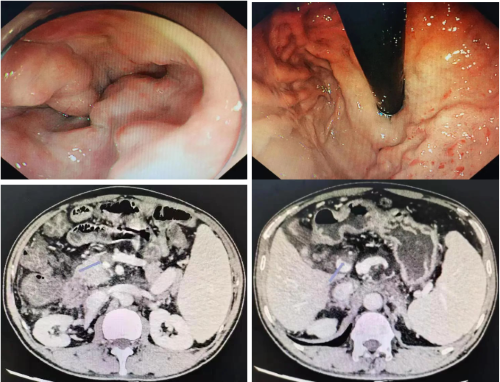

陈建勇召集科室门脉高压小组及血管介入小组核心成员进行门静脉高压MDT讨论,对老苏目前的病情进行全方位评估并制定个性化方案并给老苏进行了胃镜检查评估,提示老苏存在重度食管胃静脉曲张。门静脉CTV显示门静脉主干宽达2.2cm,门静脉主干、肠系膜上静脉及其部份分支内见低密度充盈缺损,影像诊断门脉高压、门脉主干、肠系膜上静脉及其部份分支血栓形成。根据病情,先对老苏进行了药物和内镜下治疗,但效果欠佳,远期及近期再出血风险较大,而短时间无法获取肝源进行肝移植,经过反复的讨论,并与患者和家属进行了充分沟通和交流,决定对其实行TIPS治疗。

在陈建勇指导下,科室消化介入小组核心成员顺利完成了老苏的TIPS介入手术操作。术中发现严重扩张且大量覆壁血栓形成的门静脉和胃冠状静脉,完成门体分流支架置入并栓塞了巨大曲张胃冠状静脉,老苏的门静脉压力从39mmHg降至26mmHg,大大降低了再出血的概率。